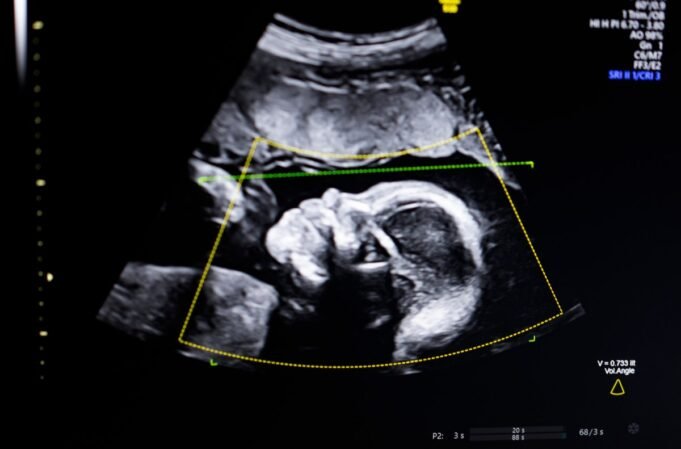

Disrupção do TechCrunch Vencedor do Battlefield 2023, Biotics AIanunciou na segunda-feira que recebeu autorização da FDA para seu software de IA. Imagens de ultrassom ajudam a detectar anomalias fetais.

A tecnologia usa IA de visão computacional para “apoiar a avaliação da qualidade do ultrassom fetal, integridade anatômica, relatórios automatizados e integração perfeita em fluxos de trabalho clínicos”, disse Bustami ao TechCrunch.

Bustami disse que os ultrassons pré-natais são a “pedra angular” do monitoramento da gravidez, mas a má qualidade da imagem pode levar a diagnósticos errados.